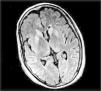

La enfermedad de Creutzfeldt-Jakob (ECJ) es una encefalopatía espongiforme producida por priones que provoca una demencia progresiva cuyas características neuropatológicas son la pérdida neuronal, la proliferación de células gliales y las vacuolas, lo que origina el aspecto de esponja. Se presentan dos casos detectados en el año 2005 en el Hospital Nuestra Señora del Prado. El primero es el de un hombre que comenzó con intensa astenia y cuadro constitucional, desarrollando una demencia en 4 meses; y el segundo caso es el de una mujer que comenzó con diplopía, cefalea y alteraciones de la marcha, desarrollando un deterioro neurológico con demencia en tres meses. En ambos casos la proteína 14.3.3 del líquido cefalorraquídeo fue positiva y el electroencefalograma mostró un patrón característico. Los estudios genéticos fueron negativos, y ambos presentaban polimorfismo del codón 129, siendo homocigotos para la metionina. Nos ha sorprendido la aparición de dos casos en menos de un año en Talavera de la Reina y nos ha hecho aumentar la vigilancia.

Creutzfeldt-Jakob disease is a prion spongiform encephalopathy that causes a rapidly progressive dementia whose neuropathological features are neuronal loss, proliferation of glial cells, and the presence of small vacuoles, which produces a spongiform appearance. Two cases detected in the year 2005 in the «Nuestra Señora del Prado» Hospital are presented. The first one is the case of a man who presented with intense malaise and weight loss, developing dementia in 4 months. The second one was a woman who presented with diplopia, headache and gait disturbances who developed severe neurological impairment with dementia in three months. In both cases the 14.3.3 protein in the cerebrospinal fluid was positive and the EEG showed a characteristic pattern. The genetic studies were negative and both were homozygous for methionine at codon 129. Given that the incidence of this disease in Castilla la Mancha is 0.6 cases/100000 inhabitants/year, the detection of 2 cases in less than a year in Talavera de la Reina (whose population is 150,000) surprised us, leading us to intensify surveillance.